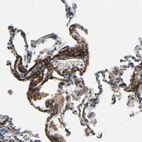

Immunohistochemical staining of human skin shows strong positivity in extracellular matrix in fibroblasts.